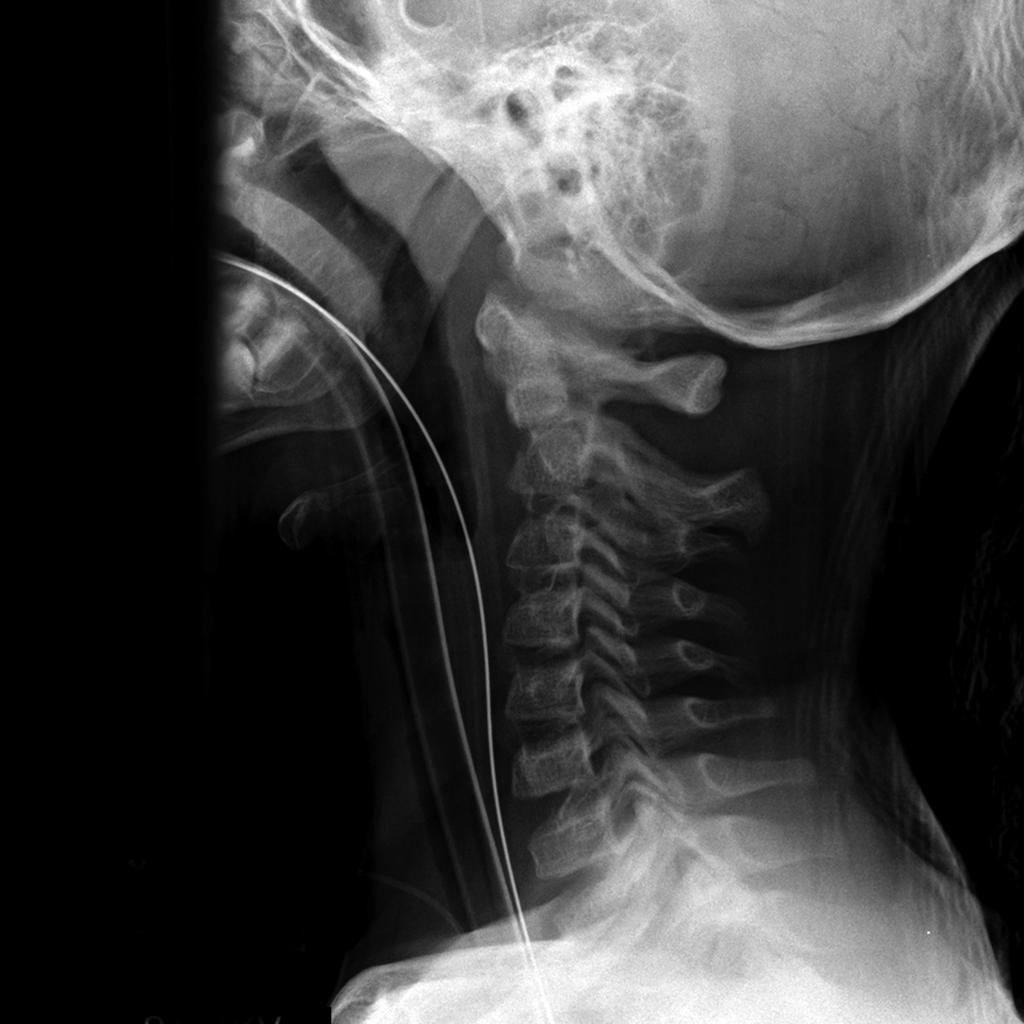

C-spine Radiographs

• Why are children more prone to high cervical spine injuries?

• By 8 to 9 years of age, cervical spine reaches adult proportions

• Cervical spine injuries in children usually occur high - from the occiput to C3 vertebra

• Fulcrum of motion in children is at the C2-C3 level rather than at the C5-C6 level in adults

• Owing to hypermobility of the c-spine because of ligamentous laxity, shallow and angled facet joints, anteriorly wedged vertebrae, and underdeveloped spinous processes

• Weak neck muscles, underdeveloped odontoid process, and large head also contribute to instability of the c-spine

• For screening, obtain lateral, AP, and odontoid views of the cervical spine

• Need for odontoid view sometimes questioned

• Some experts believe lateral view in children under 5 years sufficient

• False negative rate of single lateral view 21 to 26%

Approach

• Every lateral c-spine view should visualize at least the top of T1, of not, may need swimmer’s

• Lateral

• Upper C-spine

• Atlantodens interval (< 5 mm)

• Spinolaminar line should intersect with opisthion

• Relationship between basion and odontoid and posterior vertebral line for atlantooccipital dislocation - should be less than 12 mm (?), head usually dislocated anterior on cervical spine

• Look at odontoid

• C2 on C3 subluxation, C2 pedicles

• Lower C-spine

• Anterior vertebral body line

• Posterior vertebral body line

• Articular pillars

• Spinolaminar line

• Disc spaces should be roughly equal

• Interspinous spaces should be uniform

• Kyphotic deformity

• Prevertebral tissues (see below)